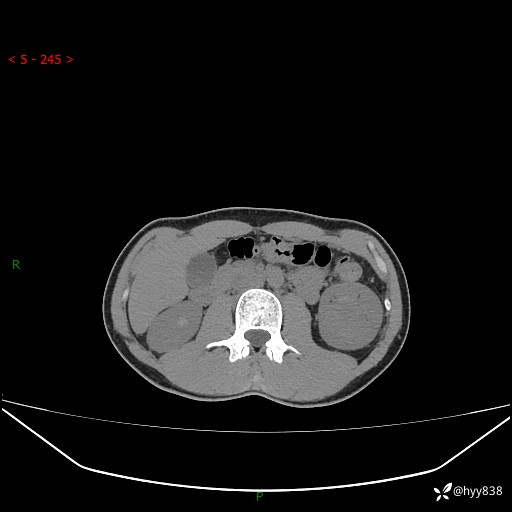

年轻男性,发现左肾占位1天。“非好病例”我不发,误诊率高---(有结果)

现病史:患者昨日中午进食后出现明显腹痛,腹泻,在我院急诊科行补液及对症治疗,双肾输尿管彩超提示左肾占位(5.2*4.3cm),平素无明显腰痛,无再发肉眼血尿等情况,现为求处理左肾占位,遂来我院,门诊以左肾占位收治入院。 患者起病以来,精神、食欲、睡眠尚可,大便可,小便如上,体力体重无明显下降。

双肾CT平扫+增强(三期)